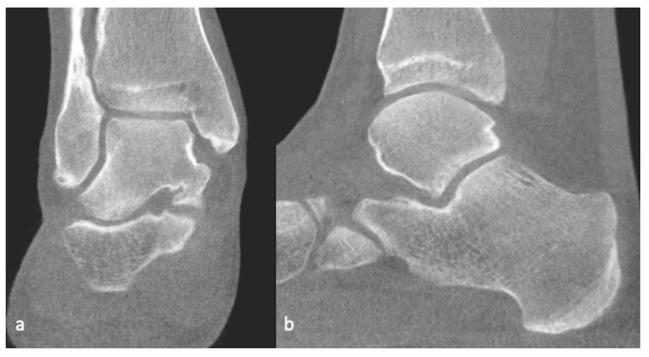

软骨及软骨损伤的影像学:综述

Imaging of Cartilage and Chondral Defects: An Overview.

A healthy articular cartilage is paramount to joint function. Cartilage defects, whether acute or chronic, are a significant source of morbidity. This review summarizes various imaging modalities used for cartilage assessment. While radiographs are insensitive, they are still widely used to indirectly assess cartilage. Ultrasound has shown promise in the detection of cartilage defects, but its efficacy is limited in many joints due to inadequate visualization. CT arthrography has the potential to assess internal derangements of joints along with cartilage, especially in patients with contraindications to MRI. MRI remains the favored imaging modality to assess cartilage. The conventional imaging techniques are able to assess cartilage abnormalities when cartilage is already damaged. The newer imaging techniques are thus targeted at detecting biochemical and structural changes in cartilage before an actual visible irreversible loss. These include, but are not limited to, T2 and T2* mapping, dGEMRI, T1ρ imaging, gagCEST imaging, sodium MRI and integrated PET with MRI. A brief discussion of the advances in the surgical management of cartilage defects and post-operative imaging assessment is also included.

摘要

健康的关节软骨对关节功能至关重要。软骨缺损,无论是急性还是慢性的,都是发病的重要原因。本综述总结了用于软骨评估的各种成像方式。虽然X线片不敏感,但仍广泛用于间接评估软骨。超声在检测软骨缺损方面显示出前景,但由于可视化不足,其在许多关节中的效果有限。CT关节造影有潜力评估关节内部紊乱以及软骨情况,尤其是在有MRI禁忌证的患者中。MRI仍然是评估软骨最受欢迎的成像方式。传统成像技术能够在软骨已经受损时评估软骨异常。因此,更新的成像技术旨在在实际可见的不可逆损失之前检测软骨的生化和结构变化。这些技术包括但不限于T2和T2*映射、双对比增强MRI(dGEMRI)、T1ρ成像、糖化学交换饱和转移(gagCEST)成像、钠MRI以及PET与MRI的联合成像。本文还简要讨论了软骨缺损手术治疗的进展以及术后成像评估。